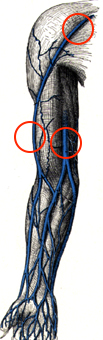

PICC

Über die Oberarmvenen eingebrachte Katheter (PICCs) sind sehr preisgünstig, haben keine Punktionskomplikationen und wegen der niedrigeren Hauttemperatur am Arm mit einer im Vergleich zum Thorax um den Faktor 1000 niedrigeren bakteriellen Kolonisation der Haut eine sehr geringe Infektrate. Bei fachmännischer Pflege können sie über Jahre benutzt werden. Die Punktion darf nicht in der Ellenbeuge erfolgen, das Lumen der Vene muß mindestens doppelt so groß sein wie der Katheter. Wegen des geringen Katheterdurchmessers (ID 1 mm) sind sie nur für langsame Infusionen wie TPN geeignet.